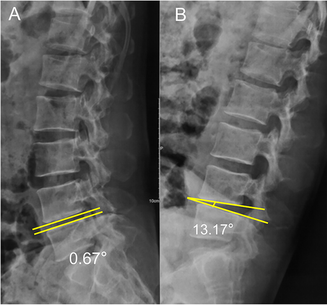

예를 들면 아래 사진에서는 척추를 과신전(A)시켰을 때와 굴곡(B)시켰을 때 척추체 사이 각(Intervertebral space angulation)이 10도 이상이기 때문에 lumbar instability 에 합당한 소견입니다.